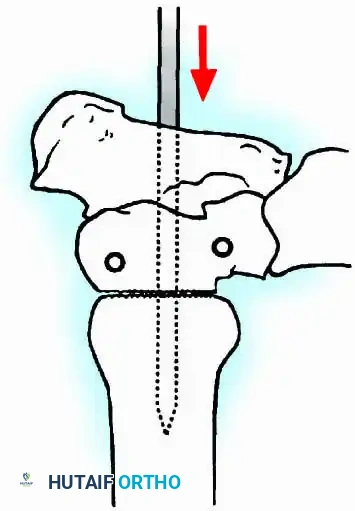

- Planar Resection (Parallel Cuts): Two parallel cuts are made—one through the distal tibial plafond and one through the talar dome—using an oscillating saw. This technique resects a minimal amount of bone but creates perfectly flat, highly vascular cancellous surfaces that allow for excellent apposition and easy posterior translation of the talus. Extramedullary alignment guides (often repurposed from total knee arthroplasty systems) can be utilized to ensure precise, parallel resections.

Internal fixation is currently the preferred method for uncomplicated ankle arthrodesis due to higher union rates, superior patient comfort, and the elimination of pin-tract infections. Biomechanical studies demonstrate that crossed, large-diameter (6.5 mm or 7.3 mm) cannulated cancellous screws provide exceptional resistance to shear and torsional forces.

A standard construct involves two or three screws:

1. A "home run" screw directed from the posterior malleolus into the anterior neck of the talus.

2. A screw from the medial malleolus into the lateral body of the talus.

3. A screw from the anterolateral tibia into the medial talar body.